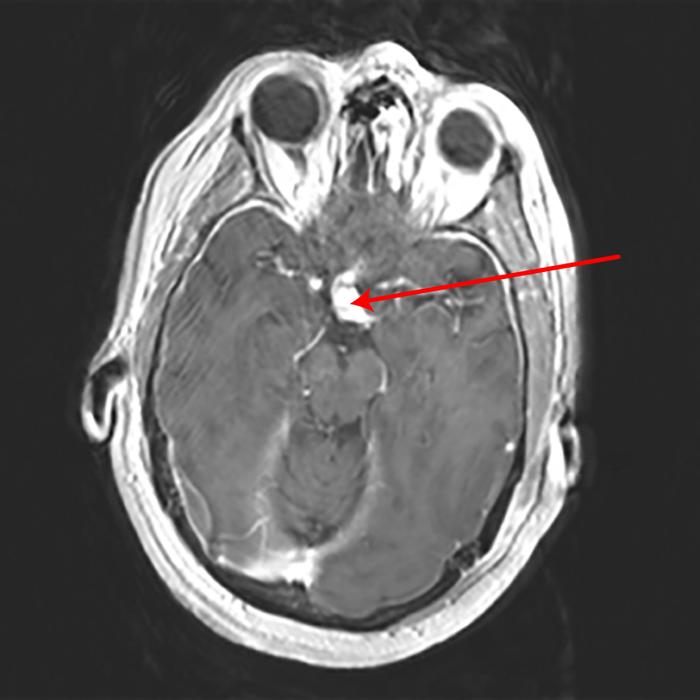

Craniofaringioma: ressonância nuclear magnética (RNM) axial pós-contraste

Do acervo de Marc C. Chamberlain; usado com permissão